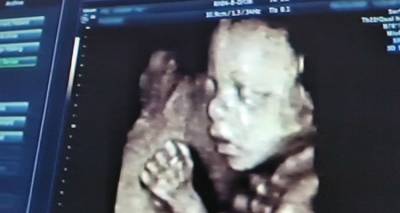

«Κανένα μυστικό δεν έχουν πλέον οι εκφράσεις του εμβρύου στη μήτρα, μιας και υπάρχει ο τετραδιάστατος υπέρηχος, που αποτυπώνει πιστά κινήσεις, εκφράσεις, χαρακτηριστικά του προσώπου αλλά κυρίως την ανατομία προσώπου, σώματος και άνω και κάτω άκρων».

Σε μια εγκυμοσύνη, το έμβρυο είναι θεωρητικά προστατευμένο από στοιχεία που θα μπορούσαν να το βλάψουν και η μητέρα είναι σε μεγάλο βαθμό υπεύθυνη ως προς την ασφάλεια του αγέννητου παιδιού.